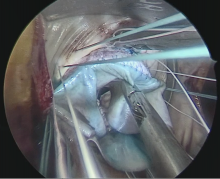

Given her age, severe MAC, and the small annular sizel, the patient was felt to not be a good candidate for an operation for the resection of the calcium bar, so an alternative approach was seeked. After counseling the patient on an off-label balloon expandable transcatheter aortic valve in MAC, and after obtaining prior authorization and institutional approval for the procedure, the patient consented to this approach. The patient was offered a right minithoracotomy mitral valve operation.

The operation was successful, with a 130 minute crossclamp. Twenty minutes of this time was spent constructing the composite TAVR valve felt/bovine pericardial composite on the back table. The patient was extubated six hours after arrival to the intensive care unit and had a 2-day stay in intensive care. She had an uneventful recovery and was discharged on postoperative day seven. Her echocardiogram prior to discharge showed no residual mitral regurgitation and mean gradient of 2 mm Hg across the valve.

Different modifications to the transcatheter balloon expandable valve have been described, but perhaps the most consistent is the suturing of the felt strip on the atrial side of the valve accompanied by a pericardial doughnut shaped washer. The rationale behind these two modifications is to minimize the risk for paravalvular leak and prevent valve migration.

A word of caution is warranted when performing this operation, and it is to factor in the time that it takes to construct the modifications on the back table. Sizing the valve using a balloon early on after resecting the anterior leaflet allows a second surgeon to perform the modification while the primary surgeon applies the annular sutures.